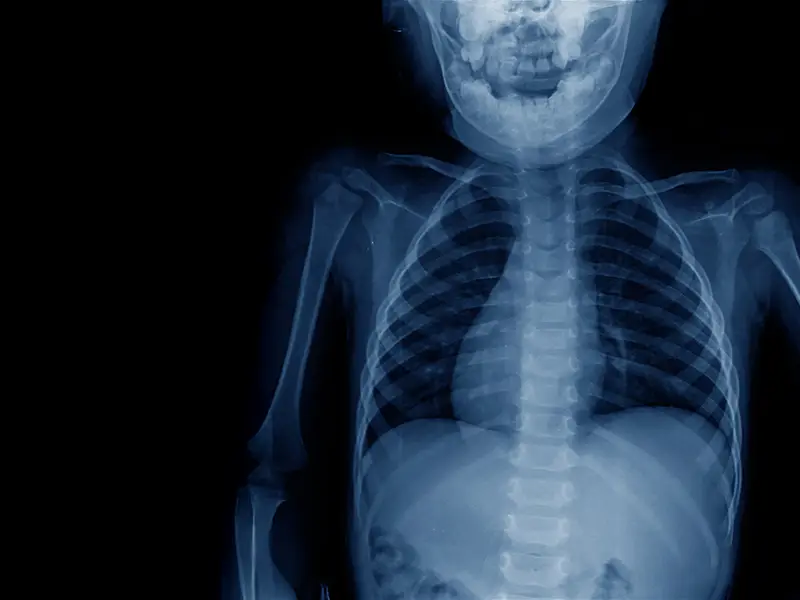

Extensive Multistage Spine Surgery Transforms A Severe Case Of Kyphoscoliosis

An adolescent patient born with congenital kyphoscoliosis, which progressed to 140 degrees kyphosis and 56 degrees scoliosis, traveled from the Philippines to New York for surgical treatment led by Lawrence Lenke, M.D., co-director of Och Spine at NewYork-Presbyterian and chief of spinal deformity surgery at NewYork-Presbyterian and Columbia. Dr. Lenke developed a treatment plan consisting of several staged procedures over six weeks, including halo gravity traction, rib resection, installation of an interbody cage, placement of rods and screws, removal of several vertebrae, placement of bone material, and irrigation and debridement to promote optimal wound healing. The surgeries successfully corrected the curvatures and fused the spine into proper position, with the patient expected to return to normal life without limitations.